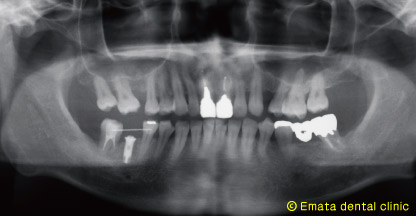

移植をおこないその移植歯を簡単な矯正(アップライト)し、今日移植歯と自分の歯の間にインプラント治療を行いました。

2歯抜歯してインプラントを2本いれるよりは、時間はかかりましたが、患者さんには喜んでいただきました。

インプラントのオペです。 |

手術後のレントゲン |